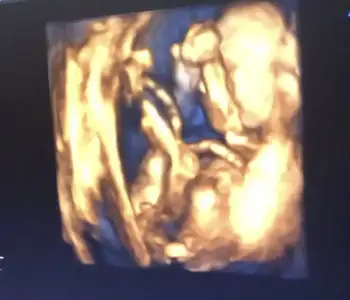

Ben bakınca küçük bir şeyler

görüyorum sanki bacağın arasında..

doktorlar da yanılabiliyorlar o yüzden anlayan biri varsa diye baksa keşke

Valla ben anlamiyorm ama doktorun eger kesin konusadiysa tekrar bi git dayanamiyosan illa ogreneyim diosan